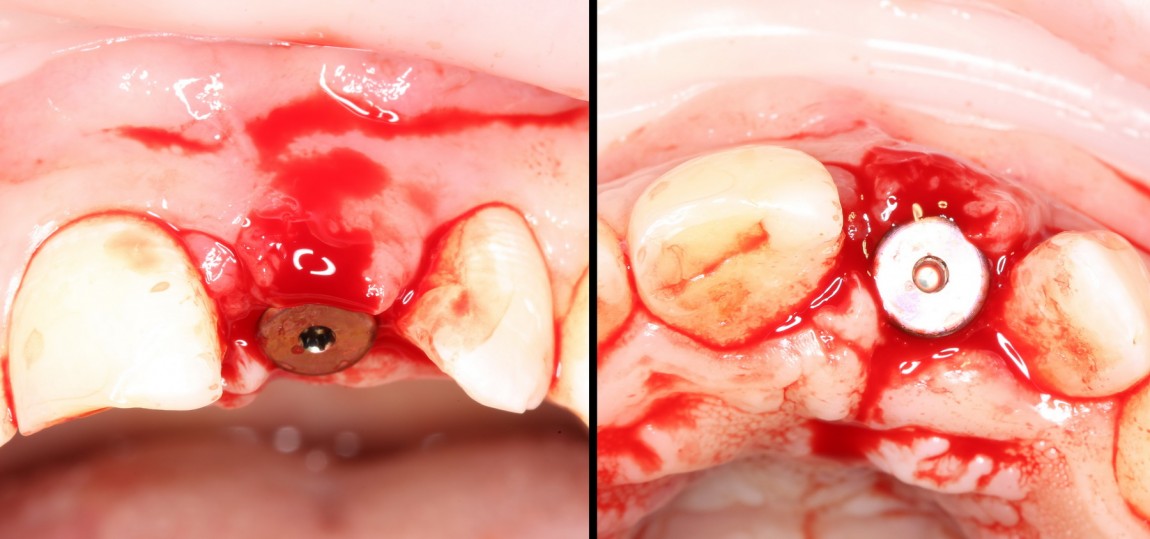

Делаем анестезию, разрез, скелетируем костную ткань:

На фотографиях хорошо видны оставшиеся после удаления объемы костной ткани. Давайте рассмотрим плюсы и минусы текущей клинической ситуации, применительно к нашему плану:

Фактически, альвеолярный гребень атрофировался по толщине примерно наполовину — это минус.

Зато с высотой все в порядке — это плюс

Немедленная нагрузка на имплантат невозможна — это минус. Почему? (см. Факторы…)

Достаточный объем кератинизированной десны, который даст нам возможность герметично запечатать послеоперационную рану — это, несомненно, тоже плюс. (вспомним факторы успеха остеопластической операции, часть III)

Ну и, оставшиеся объемы костной ткани позволят нам установить и правильно позиционировать имплантат — это главный плюс. А значит, мы обойдемся одной операцией вместо двух.

Лунка готова, устанавливаем имплантат:

Это Nobel Replace CC 3.5×13 mm. Оптимальный размер импланта для работы в этом клиническом случае.

Продолжим нашу работу. Имплантат установлен:

Работа закончена? Отнюдь, нет. Теперь наша задача — восстановить утраченные объемы костной ткани вокруг импланта. Ибо, как вы видите на фото, его вестибулярная поверхность, практически, просвечивает. И, если ничего не делать, дальше будет только хуже.